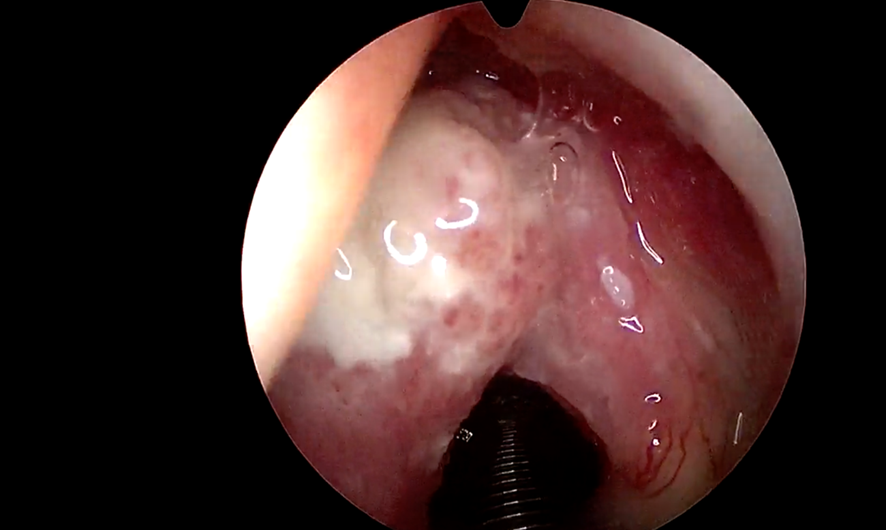

Assim como acontece com o câncer da tireoide, em que a cirurgia passa a ser o tratamento assertivo, sem a necessidade de complementação com quimioterápicos e radiação, no câncer de laringe, para alguns casos, está indicado a ressecção a laser, a cirurgia endoscópica a laser. Eu, particularmente, gosto da ressecção a laser. Quando bem indicada evita a radioterapia, que por vezes é uma opção nos canceres da laringe. A Radioterapia tem mais efeitos colaterais do que a cirurgia a laser isoladamente.

As principais vantagens do laser são a recuperação rápida e o retorno às atividades cotidianas e à vida social. Na maioria dos casos, esse tratamento não requer o uso da traqueostomia! Outro ponto favorável desta técnica cirúrgica é o menor risco de sequelas, com índices positivos de preservação da voz.